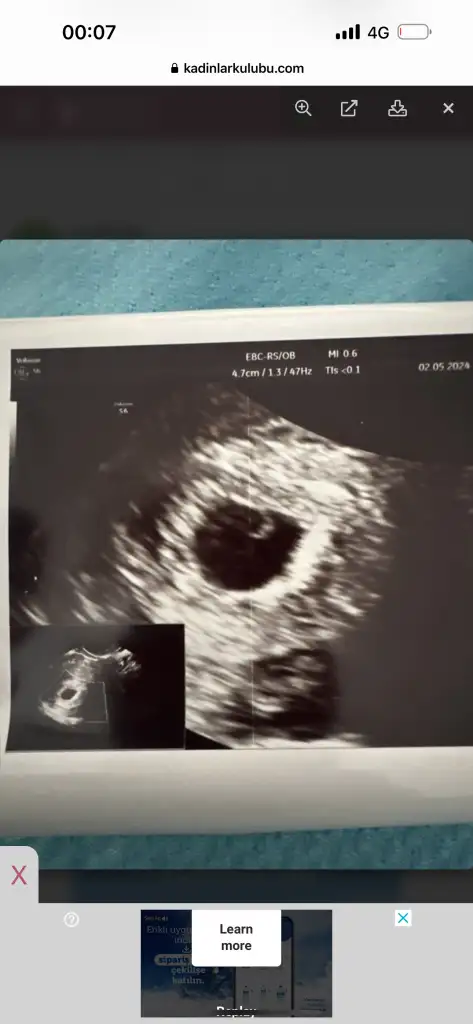

Nolur banada yardım edin . Ben bugün doktora gittim kese boyutu 18.42mm . Bebeği göremedi . Haftaya gel bebek yoksa kürtaj olucaksın dedi görseli ekliyorum. Başına gelen car mı??? 6+5 haftalık görünüyorKızlar selam yardımınıza ihtiyacım var.

Son adet tarihine göre kaç haftalıksiniz.Benim başıma geldi daha yeni düşük yaptımNolur banada yardım edin . Ben bugün doktora gittim kese boyutu 18.42mm . Bebeği göremedi . Haftaya gel bebek yoksa kürtaj olucaksın dedi görseli ekliyorum. Başına gelen car mı??? 6+5 haftalık görünüyor

Aynı şeyi kasım ayında yaşadım ne çektiğimi bir Allah bir ben bilirim ilk başta her iki günde bir beta verdim bana yükselmez dış gebelik dediler sonra yükseldi azar azar daha sonra kese oluşmaz dediler kese de oluştu ama kesenin içinde bebek oluşmadı uygulamaya göre 9+3 ama doktor keseye göre 6+2 dedi ve her iki günde bir ultrason yaptırdım iki farklı hastanede takip ettim ama en sonunda kürtaj dediler ilaç verip kürtaj yaptılarNolur banada yardım edin . Ben bugün doktora gittim kese boyutu 18.42mm . Bebeği göremedi . Haftaya gel bebek yoksa kürtaj olucaksın dedi görseli ekliyorum. Başına gelen car mı??? 6+5 haftalık görünüyor